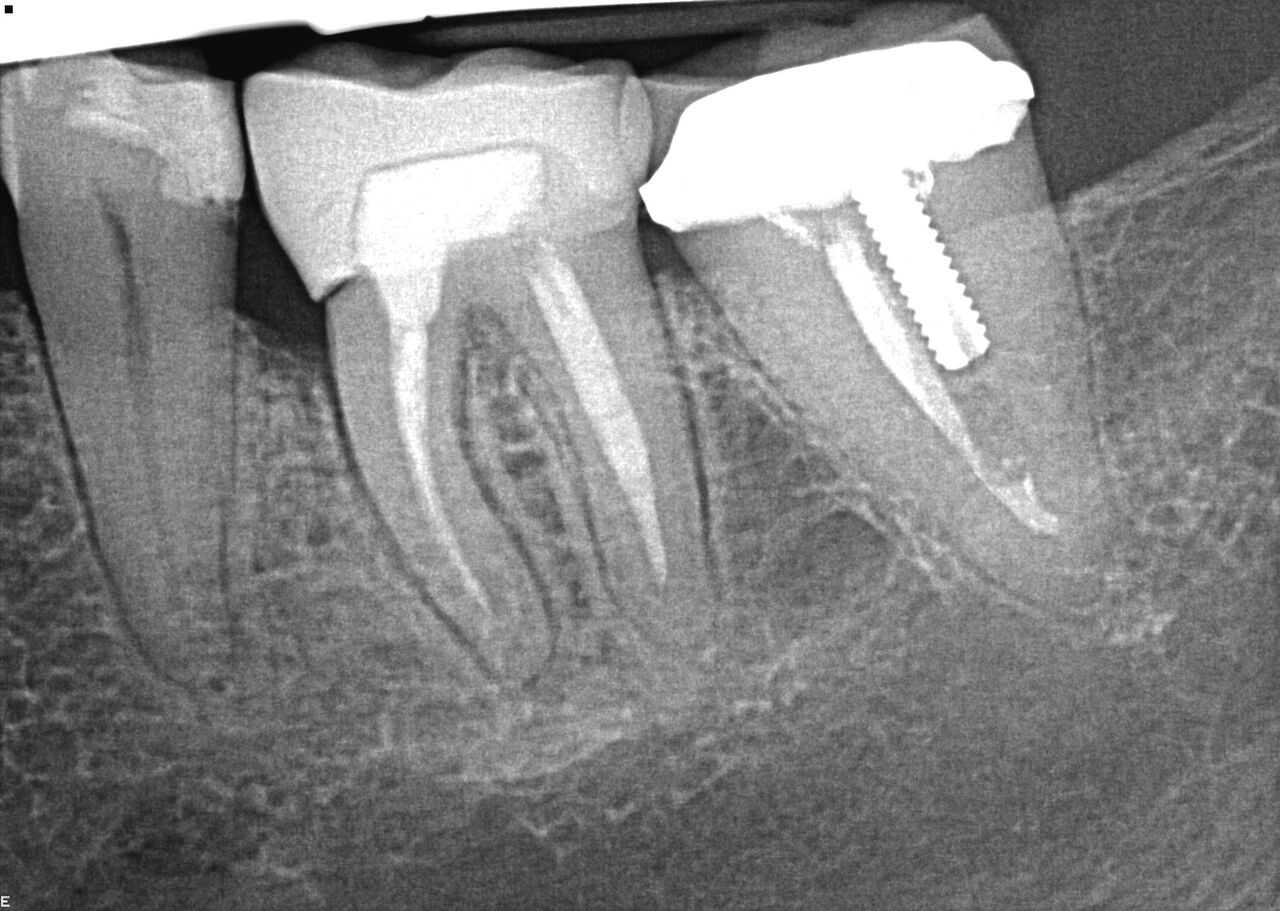

(1.) Case 1 initial radiograph of No. 19.

Figure 1

(2.) Immediate implant of No. 19 with temporization abutment.

Figure 2

(4.) Radiograph showing immediate implant of No. 19 with immediate restoration day of surgery.

Figure 4

A 63-year-old woman presented with severe pain on biting of tooth No. 19 (Figure 1). Clinically there was pain on percussion and significant periodontal probing along the mesial root. The patient was anesthetized with infiltration anesthesia and the crown was horizontally sectioned from the lingual of the tooth. The remaining tooth was sectioned so the roots could be extracted individually. The socket was fully debrided and an implant was placed (Figure 2), which was prosthetically correct and stabilized in excess of 45 Ncm. The bone was milled to allow for unimpeded placement of a temporization abutment. The initial crown was revised to be the temporary crown in infraocclusion. Cement was extruded extraorally (Figure 3) prior to seating of the temporary restoration. The socket was sealed with the temporary crown and there were no sutures or bone graft (Figure 4 and Figure 5).